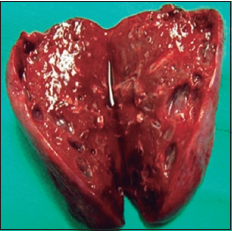

Imágenes y Cirugía

Natalia González Alcolea, María Dolores Chaparro Cabezas, Félix Martínez Arrieta, Victor Sánchez Turrión